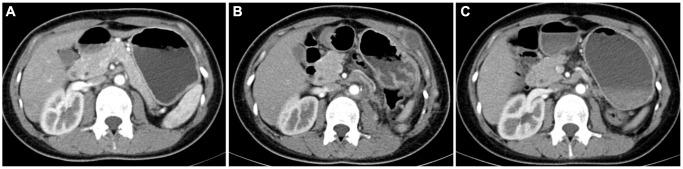

Therapeutic strategies and predictive models for Xp11.2 translocation/TFE3 gene fusion renal cell carcinoma in adults based on data of two Chinese medical centers.

Univariate and multivariate logistic regression analyses demonstrated that age, sex, BMI, smoking, eosinophils, and LDL were independent predictors of TFE3-RCC. Therefore, a predictive nomogram for TFE3-RCC, which had good discriminatory power (AUC = 0.796), was constructed. External validation (AUC = 0.806) also revealed good predictive ability. The calibration curves displayed good consistency between the predicted and observed incidences of TFE3-RCC. Invasion of regional lymph nodes, tyrosine kinase inhibitors, and surgical methods were independent factors associated with progression. Tyrosine kinase inhibitors are independent prognostic factors.